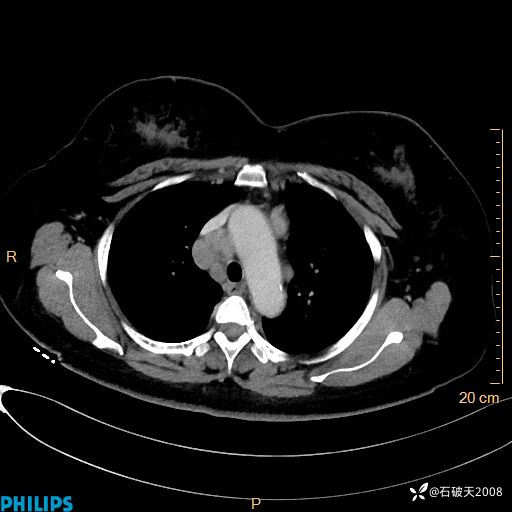

肺结节病?纵膈型肺癌?淋巴瘤?有点意思,欢迎围观

女 52岁 主 诉:咳嗽10余天,咳痰2天。

现病史:10余天前无明显诱因出现咳嗽,呈阵发性干咳,伴咽喉部发痒,无咽痛,无咳痰,无鼻塞、流涕、打喷嚏,无发热、畏寒、寒颤,无头痛、头晕,无胸闷、胸痛,无反酸、烧心,无腹痛、腹泻,无尿频、尿急,无皮疹等,在当地诊所求治,给予口服药物治疗(具体不详),病情无好转。遂在当地社区卫生服务中心开具口服药物治疗(具体不详),疗效欠佳。2天前出现咳痰,在我院门诊求治,行胸部CT提示肺部感染,建议住院,患者要求口服药物治疗,目前仍咳嗽、咳白色粘痰,白天量多,夜间自觉喉部喘鸣音,遂再次来院就诊,以“肺部感染”为诊断收入院。发病以来,神志清,精神可,饮食可,夜间睡眠差,大小便正常,近期体重无明显变化。

肺窗